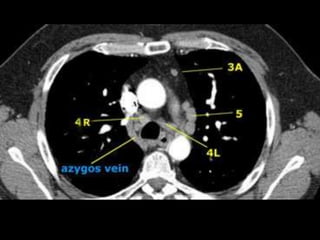

• Mediastinales superiores:

– 1) Mediastinales altos: encima de una linea que pasa por el borde

superior de la vena innominada izquierda, al cruzar la traquea.

– 2R y 2L) Paratraqueales superiores derechos e izquierdos: encima

de una linea que pasa por el borde superior del arco aórtico.

– 3A) Prevasculares.

– 3P) Retrotraqueales.

– 4R y 4L) Paratraqueales inferiores derechos e izquierdos: por

encima de una linea que pasa por el borde superior del

bronquiofuente respectivo, a nivel de la salida del bronquio lobar

superior.

Ganglios

• Aórticos

– 5) Subaórticos: en la ventana aortopulmonar, laterales al

ligamento arterioso, próximos a la rama izquierda de la arteria

pulmonar.

– 6) Paraaórticos: en la cara anterior y lateral de la aorta

ascendente, el cayado y el tronco braquiocefálico.

• Mediatinales inferiores:

– 7) Subcarinales:

– 8) Paraesofagicos:

– 9) Del ligamento pulmonar

Ganglios • Mediastinales superiores: –1) Mediastinales altos: encima de una linea que pasa por el borde superior de la vena innominada izquierda, al cruzar la traquea. – 2R y 2L) Paratraqueales superiores derechos e izquierdos: encima de una linea que pasa por el borde superior del arco aórtico. – 3A) Prevasculares. – 3P) Retrotraqueales. – 4R y 4L) Paratraqueales inferiores derechos e izquierdos: por encima de una linea que pasa por el borde superior del bronquiofuente respectivo, a nivel de la salida del bronquio lobar superior.

Ganglios • Aórticos – 5)Subaórticos: en la ventana aortopulmonar, laterales al ligamento arterioso, próximos a la rama izquierda de la arteria pulmonar. – 6) Paraaórticos: en la cara anterior y lateral de la aorta ascendente, el cayado y el tronco braquiocefálico. • Mediatinales inferiores: – 7) Subcarinales: – 8) Paraesofagicos: – 9) Del ligamento pulmonar